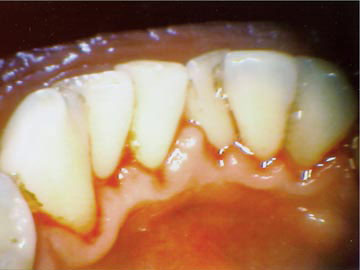

The excretes of these bacteria are acids and toxins, which attack the teeth, the gum and the jaw bone and result in caries (tooth decay), gum bleeding and periodontitis (loose teeth).

The oral cavity is populated with countless bacteria, which stick on the surface of the teeth and produce the dental plaque. In some areas the plaque hardens and cannot be removed by simple tooth brushing.